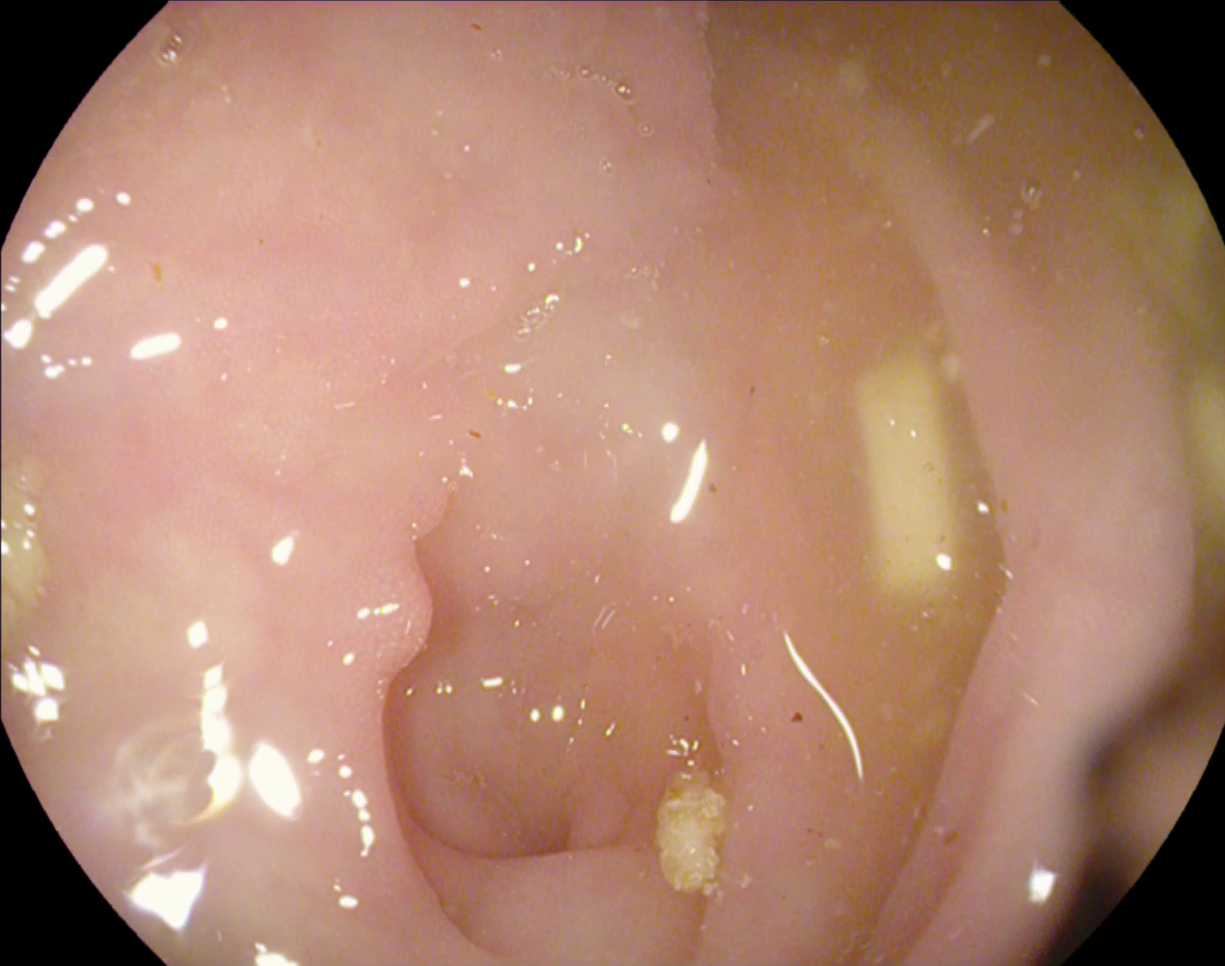

Figure 1: Polyp visual aspects have a wide variety in terms of shape and color. Four different polyps sampled from the different databases considered in this work: (a) Kvasir-Seg [19], (b) CVC-ClinicDB [5], (c) CVC-ColonDB [4], (d) ETIS [29].

The large bowel within the human gastrointestinal tract can be affected by different diseases, among which, Colorectal Cancer (CRC) is particularly concerning. CRC represents the second most common cancer type in women and third most common for men [15]. Gastro-intestinal polyps are known precursors of this type of cancer [34], being present in almost half of the patients over 50 undergoing screening colonoscopies [31]. This kind of lesions show a wide range of shapes and visual appearances, as shown in Fig. 1, turning its identification and segmentation into a challenging problem.